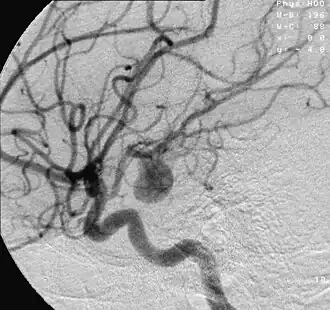

Een aneurysma (Grieks ἀνεύρυσμα, meervoud aneurysmata) is een plaatselijke verwijding van een (meestal) slagaderlijk bloedvat, als gevolg van een ter plaatse zwakke vaatwand. Het meest voorkomend is een aneurysma van de aorta, de slagader in de buik of het abdomen. Men spreekt in dat geval van een abdominaal aorta-aneurysma (AAA). Een aneurysma van de aorta ter hoogte van de borstkas, is een thoracaal aorta-aneurysma (TAA). Een aneurysma gaat meestal niet gepaard met klachten.

Symptomen

Diagnose (opsporing) en behandeling van een AAA

Vanwege het levensbedreigende karakter, is het aan te raden een verdenking op een aneurysma goed te laten onderzoeken. Lichamelijk onderzoek alleen sluit een aneurysma nooit uit. Als gouden standaard voor het aantonen van een aneurysma wordt een echografie van de buik gebruikt. Hierbij kan men nauwkeurig de juiste diameter van het verwijde bloedvat bepalen. Hierbij houdt men de grootst te meten voor-achterwaartse diameter, de Anterior-Posterior- of AP-diameter, aan. Als arbitraire grens wordt een diameter van 55 mm gebruikt bij mannen en 50 mm bij vrouwen. Uit onderzoek is gebleken dat vanaf deze diameter het risico op een vaatbreuk of ruptuur reëel is, en de risico's van een operatie niet meer opwegen tegen het risico op scheuren.

Een CT-scan met contrastvloeistof laat precies zien hoe de vaatboom rond de aorta eruitziet. Dit bepaalt ook of men laparo-tomisch, via het openen van de buikholte, of endovasculair (vanuit de vaten na benadering in de liesslagader(s)) opereert. Men kiest respectievelijk voor het inhechten van een aortabifurcatieprothese, ook wel broekprothese genoemd, of een endovasculaire stent op maat. Laatstgenoemde procedure staat bekend als EVAR; Endovascular Aneurysm Repair.